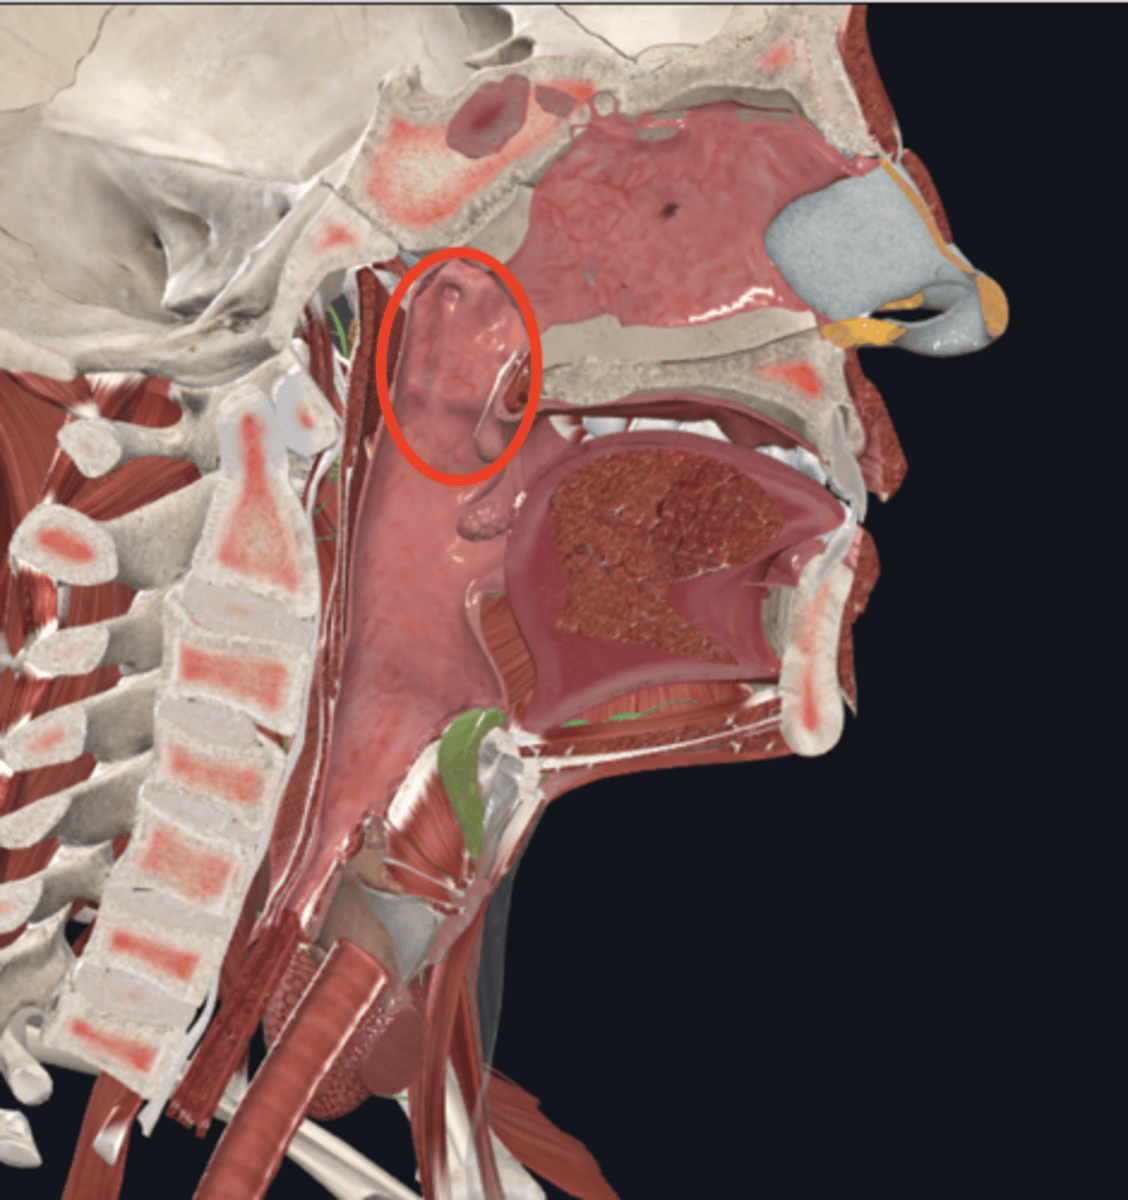

name the circled region

oropharynx

name the circled region

laryngopharynx

name the circled region